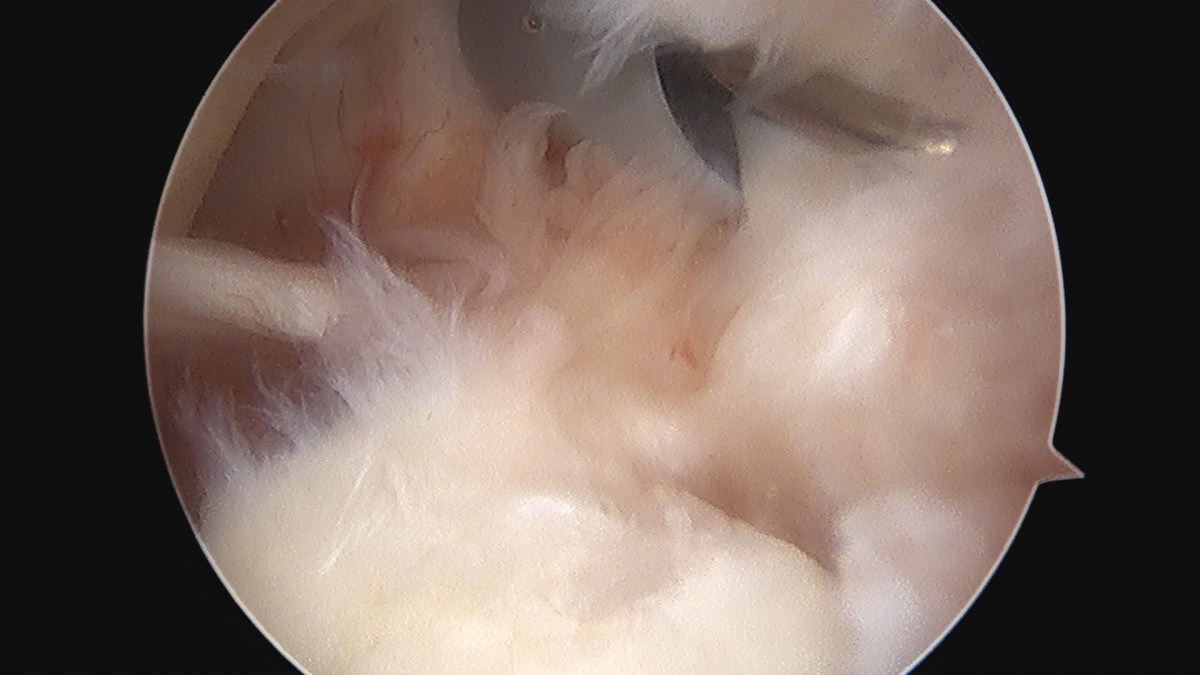

이재상원장님 어깨 이두박건 절제술 정하O 환자

dae765e4d9ac96aee867c9d6292d8784_1758006941_0303.jpg